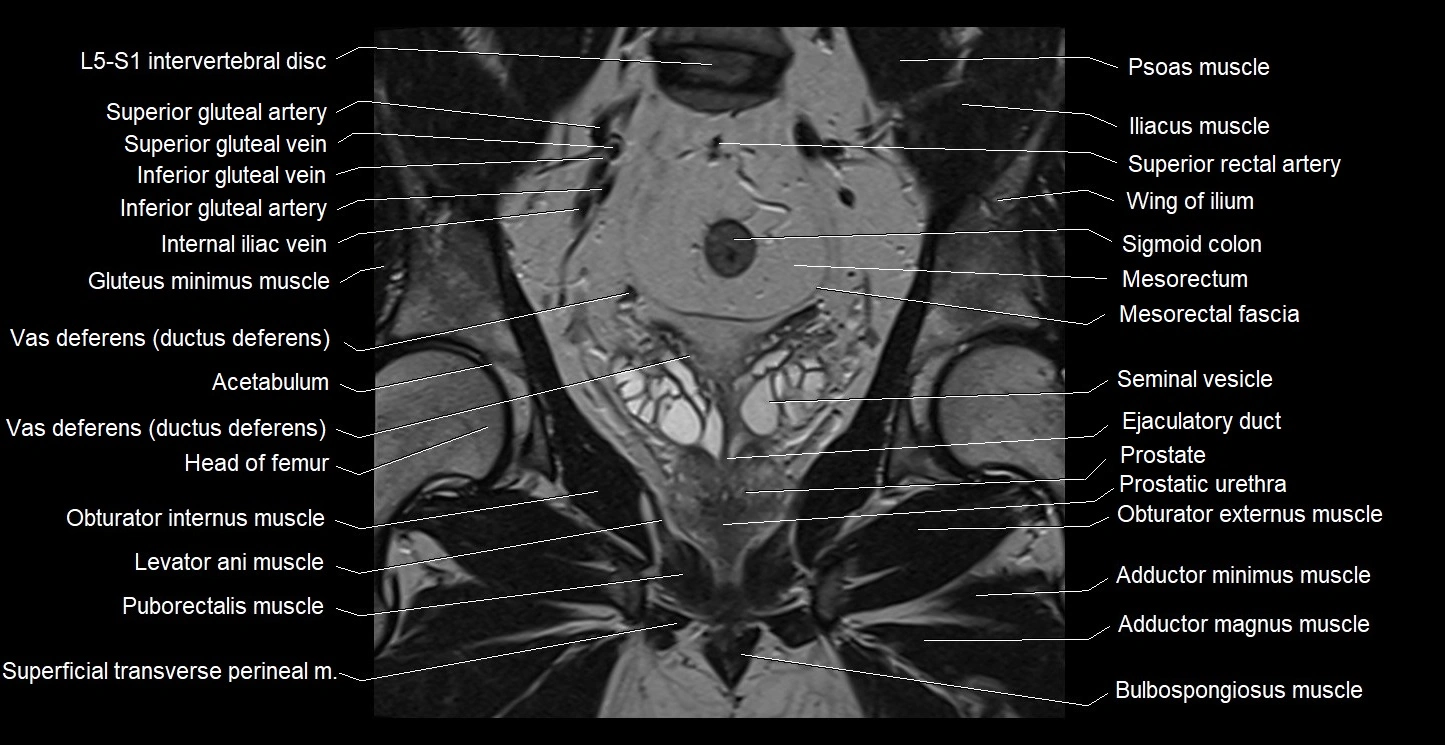

- Acetabulum

- Ejaculatory duct

- Gluteus maximus muscle

- Gluteus minimus muscle

- Head of femur

- Internal iliac artery

- Internal iliac vein

- Levator ani muscle

- Mesorectal fascia

- Mesorectum

- Obturator externus muscle

- Obturator internus muscle

- Pectineus muscle

- Peripheral zone of prostate

- Prostatic urethra

- Puborectalis muscle

- Seminal vesicle

- Sigmoid colon

- Vas deferens